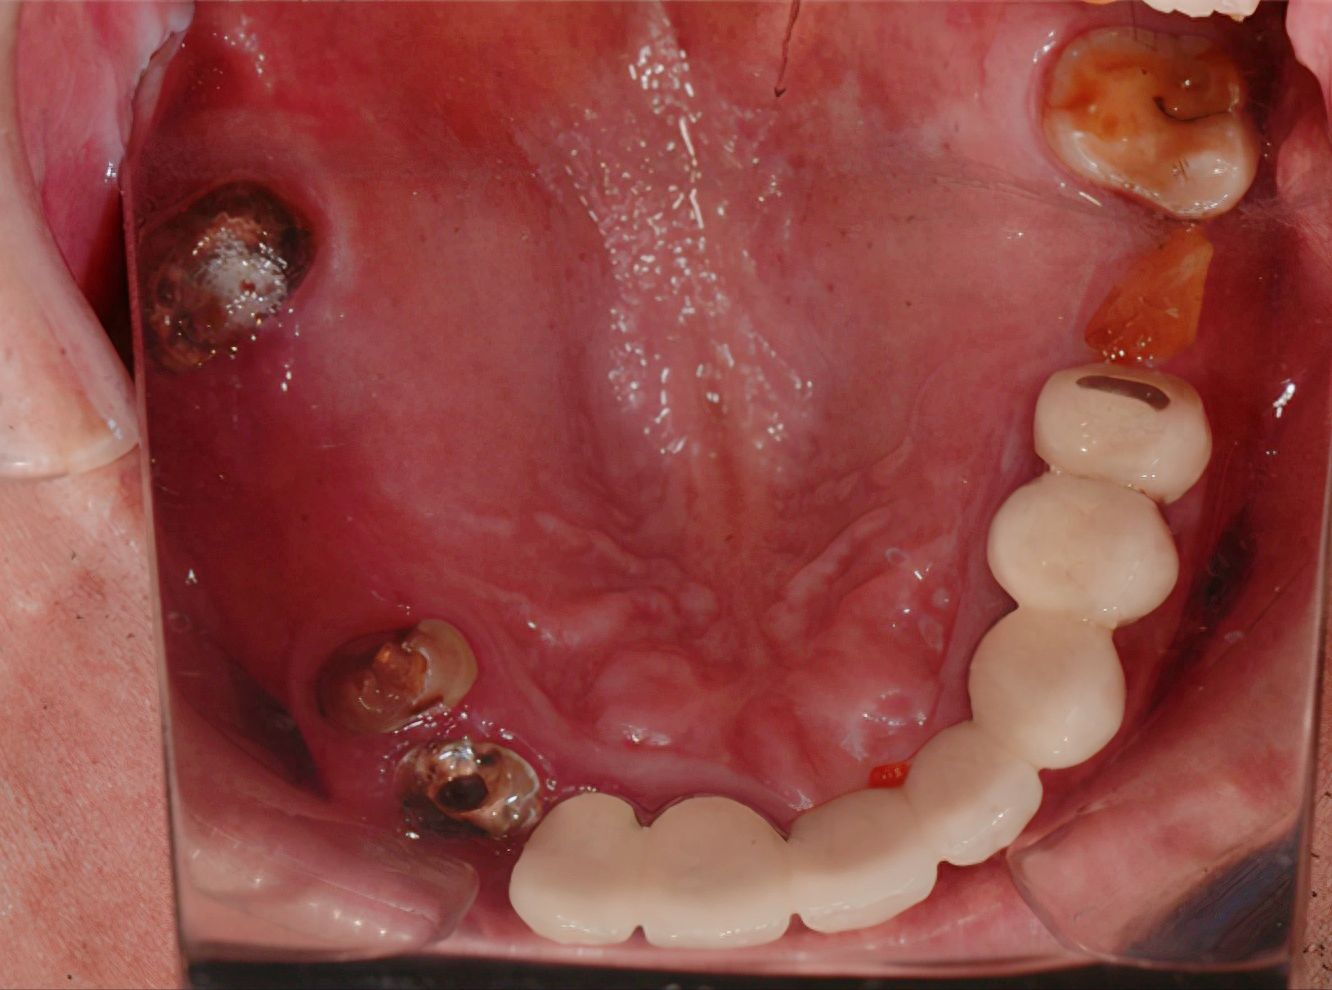

一位患者在無錫維樂口腔醫(yī)院接受了種植牙治療,她因意外導致門牙受損,影響了日常生活。經(jīng)過詳細檢查,醫(yī)生推薦了種植牙技術(shù),并介紹了成功案例。盡管價格較高,但患者決定接受治療。手術(shù)順利進行,經(jīng)過數(shù)月的恢復,患者牙齒恢復良好,不僅舒適堅固,而且美觀白皙,讓她重新?lián)碛凶孕排c舒適的笑容。